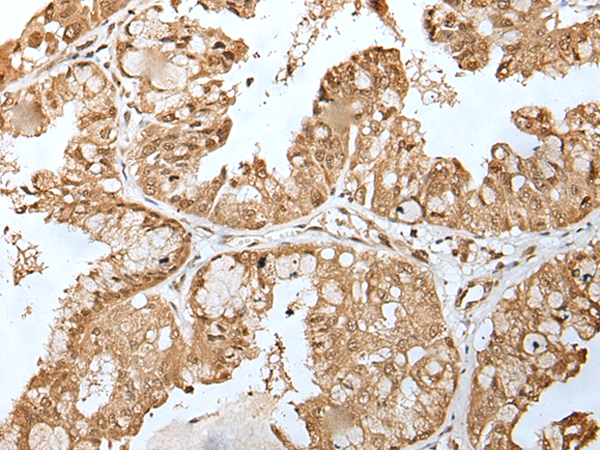

IHC (Immunohistochemistry)

(The image is immunohistochemistry of paraffin-embedded Human esophagus cancer tissue using (ZNF202 Antibody) at dilution 1/30.)